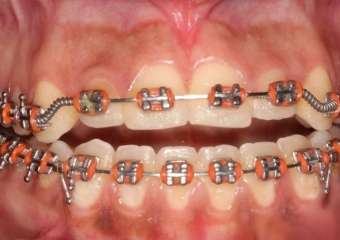

Mordida após a cirurgia  - Clínica Cliniface

Mordida após a cirurgia